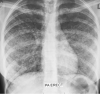

Case presentation: A 37-year-old Ugandan woman was diagnosed with HIV infection 8 days prior to her referral to our center. She was antiretroviral naïve. Her chief complaints were worsening cough, difficulty in breathing, fever and altered mental status for 3 days with a background of a 1-month history of coughing with associated drenching night sweats and weight loss. The reverse transcriptase-polymerase chain reaction for SARS-CoV-2 of her nasopharyngeal swab sample was positive. Chest radiograph demonstrated military pattern involvement of both lungs. The serum and cerebrospinal fluid cryptococcal antigen tests were positive. Urine lipoarabinomannan and sputum GeneXpert were positive for Mycobacterium tuberculosis. Computed tomography of the brain showed a large acute ischemic infarct in the territory of the right middle cerebral artery. Regardless of the initiation of treatment, that is, fluconazole 1200 mg once daily, enoxaparin 60 mg, intravenous (IV) dexamethasone 6 mg once daily, oral fluconazole 1200 mg once daily, IV piperacillin/tazobactam 4.5 g three times daily and oxygen therapy, the patient passed on within 36 hours of admission.